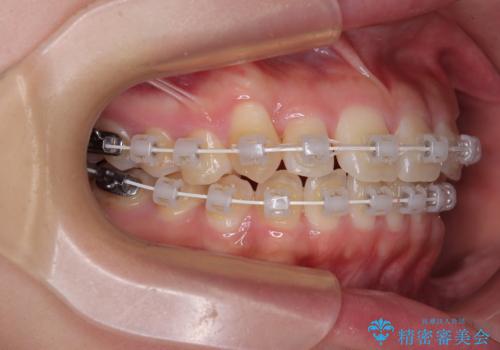

- 審美装置

- 8ヶ月

- 上下前歯のデコボコを気にして来院された患者様です。

ワイヤー矯正でもマウスピース矯正でも可能でしたが、短期間で、自身の手を煩わせることなく治療を行いたいとのことで、ワイヤー装置にて矯正治療を行うこととしました。

僅か8ヶ月という短期間で、綺麗な歯列に仕上がりました。